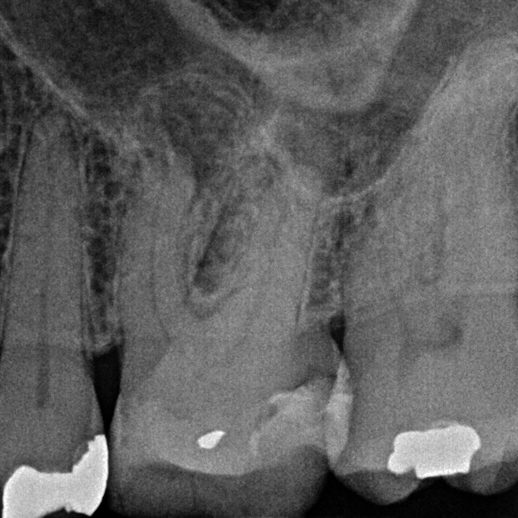

A missed MB2 canal is one of the main causes of endodontic failure in maxillary molars. In cases of irreversible pulpitis, it is responsible for ongoing temperature sensitivity. In necrotic cases, residual bacteria will increase the risk of infection (Figure 4).

Figure 4: Patient was referred for the root canal retreatment of UR6. The tooth had been treated privately with her general dentist three years ago; the root canal treatment had been carried out to a good standard (under rubber dam isolation, three canals cleaned, shaped, disinfected using sodium hypochlorite and obturated to length). The patient did not have significant pain but the tooth did not ‘feel right’ and was affecting her function. Root canal retreatment was carried out and an additional MB2 canal was located. The patient’s symptoms settled immediately following treatment and she was advised to proceed with a cuspal coverage restoration.